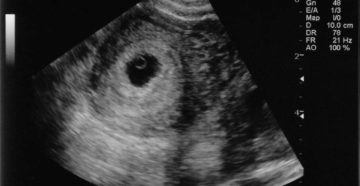

Развитие плода: 3 недели беременности Третья неделя беременности – самое начало важного и долгого периода…